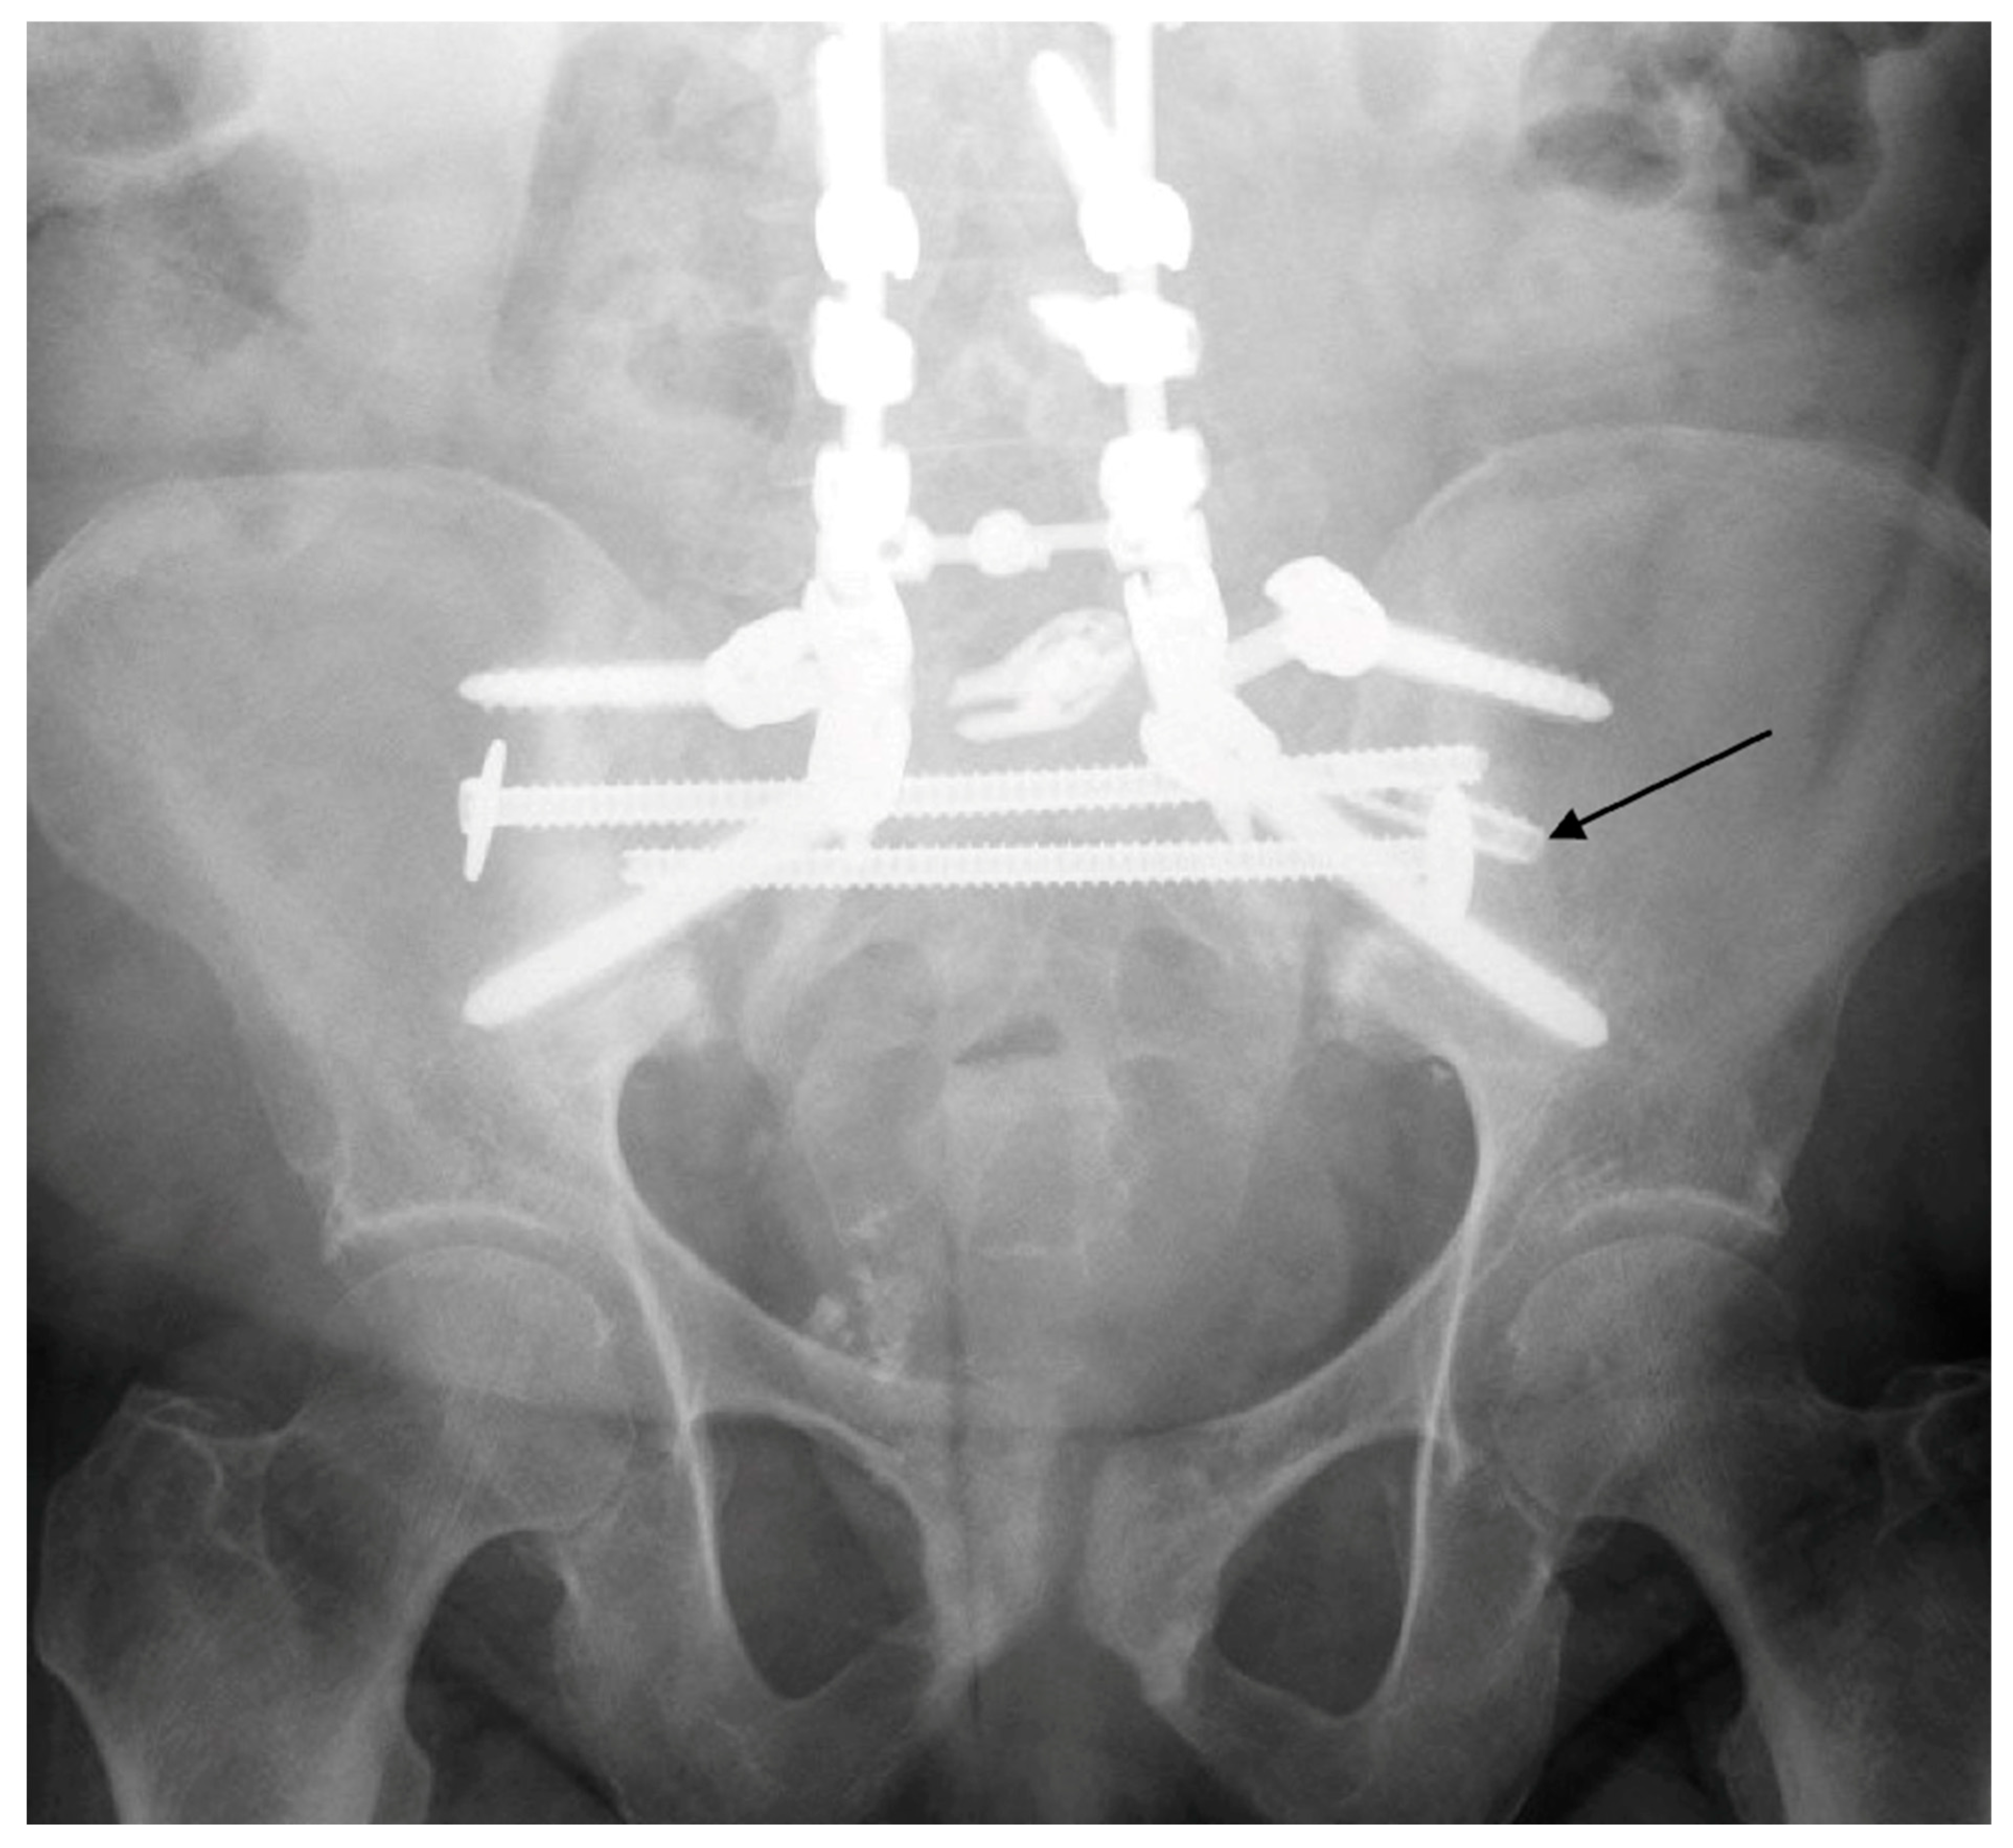

5. Techniques and Considerations in Spinopelvic Fixation: Sequence, Reduction, and Avoiding Complications

6. Spinopelvic Fixation Percutaneous Technique